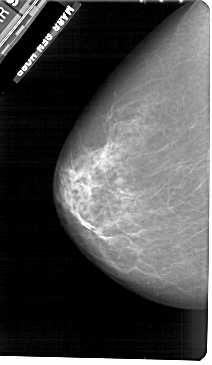

A_1908_1.LEFT_CC

LEFT_CC LINES 5461 PIXELS_PER_LINE 3166 BITS_PER_PIXEL 12 RESOLUTION 43.5 NON_OVERLAY